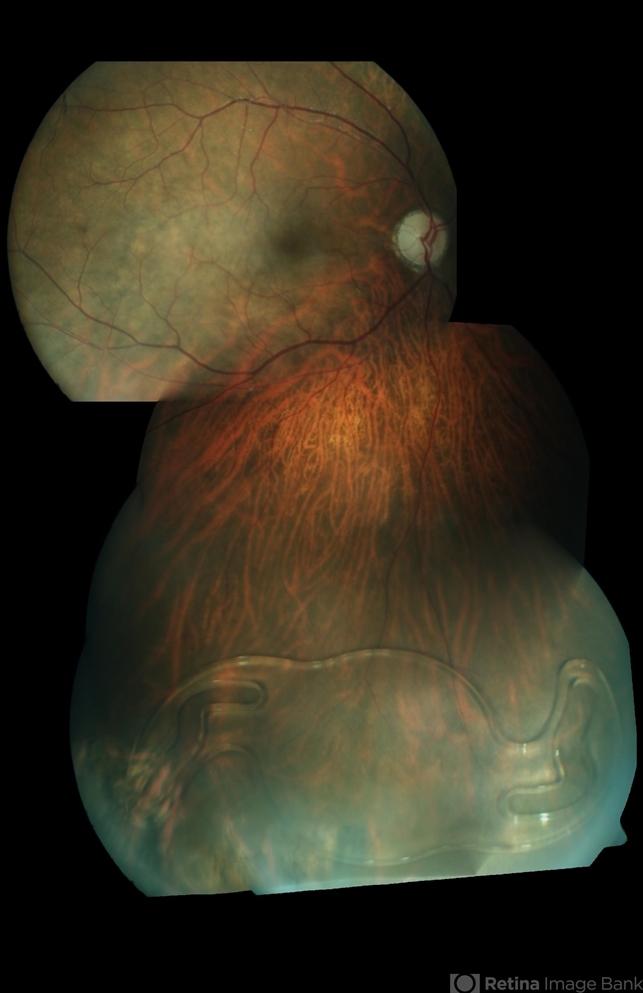

- dislocated intraocular lens (IOL)

- Fundus photograph of an 61-year-old male with dislocated IOL in vitreous cavity.